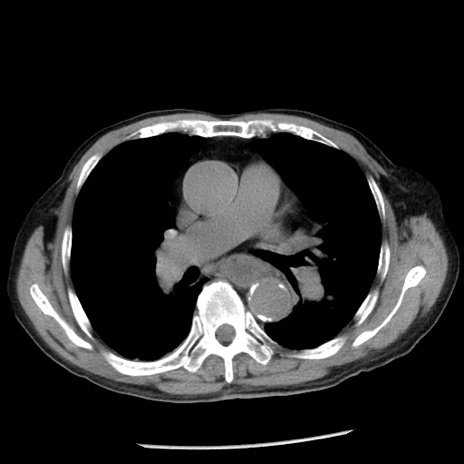

冠状断像

症例26(横断像)

【症例】80歳代男性

【主訴】嘔吐

【現病歴】昨晩2回嘔吐あり、今朝になっても嘔吐あり。来院。

【既往歴】胃潰瘍

【身体所見】意識清明、BT 37.6℃、BP 166/95mmHg、HR 100bpm、SpO2 97%、腹部:平坦・軟、腸蠕動音聴取良好、圧痛なし。

【データ】WBC 21900、CRP 1.46